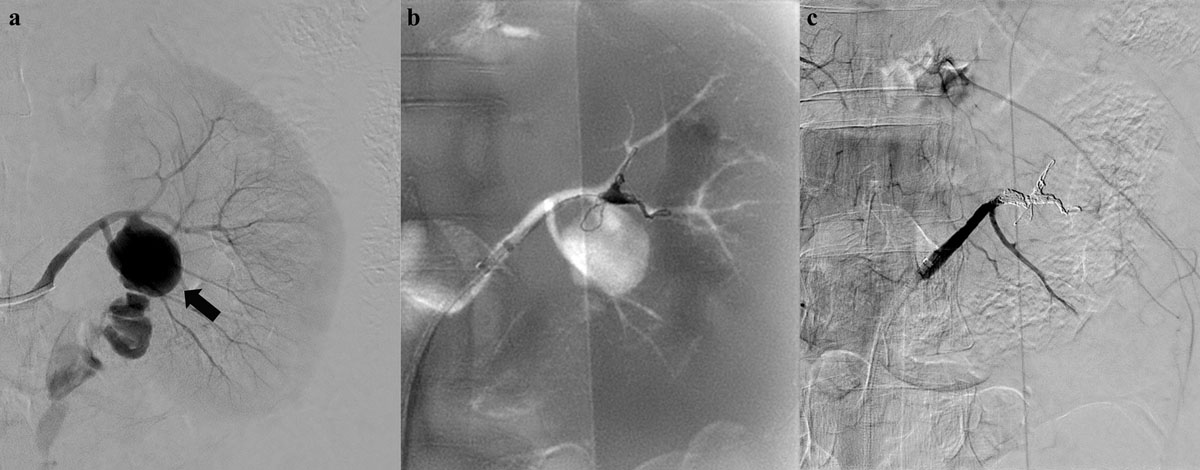

Figure 3

A 49-year-old woman presenting with acute left flank pain without trauma history. (a) An initial left renal angiogram reveals a huge pseudoaneurysm (black arrow) and contrast extravasation at proximal segment of anterior division. (b) Superselective embolization of anterior division using coaxial microcatheter system and detachable microcoils. (c) Complete cessation of active bleeding on final angiogram with preserved flow of posterior division.